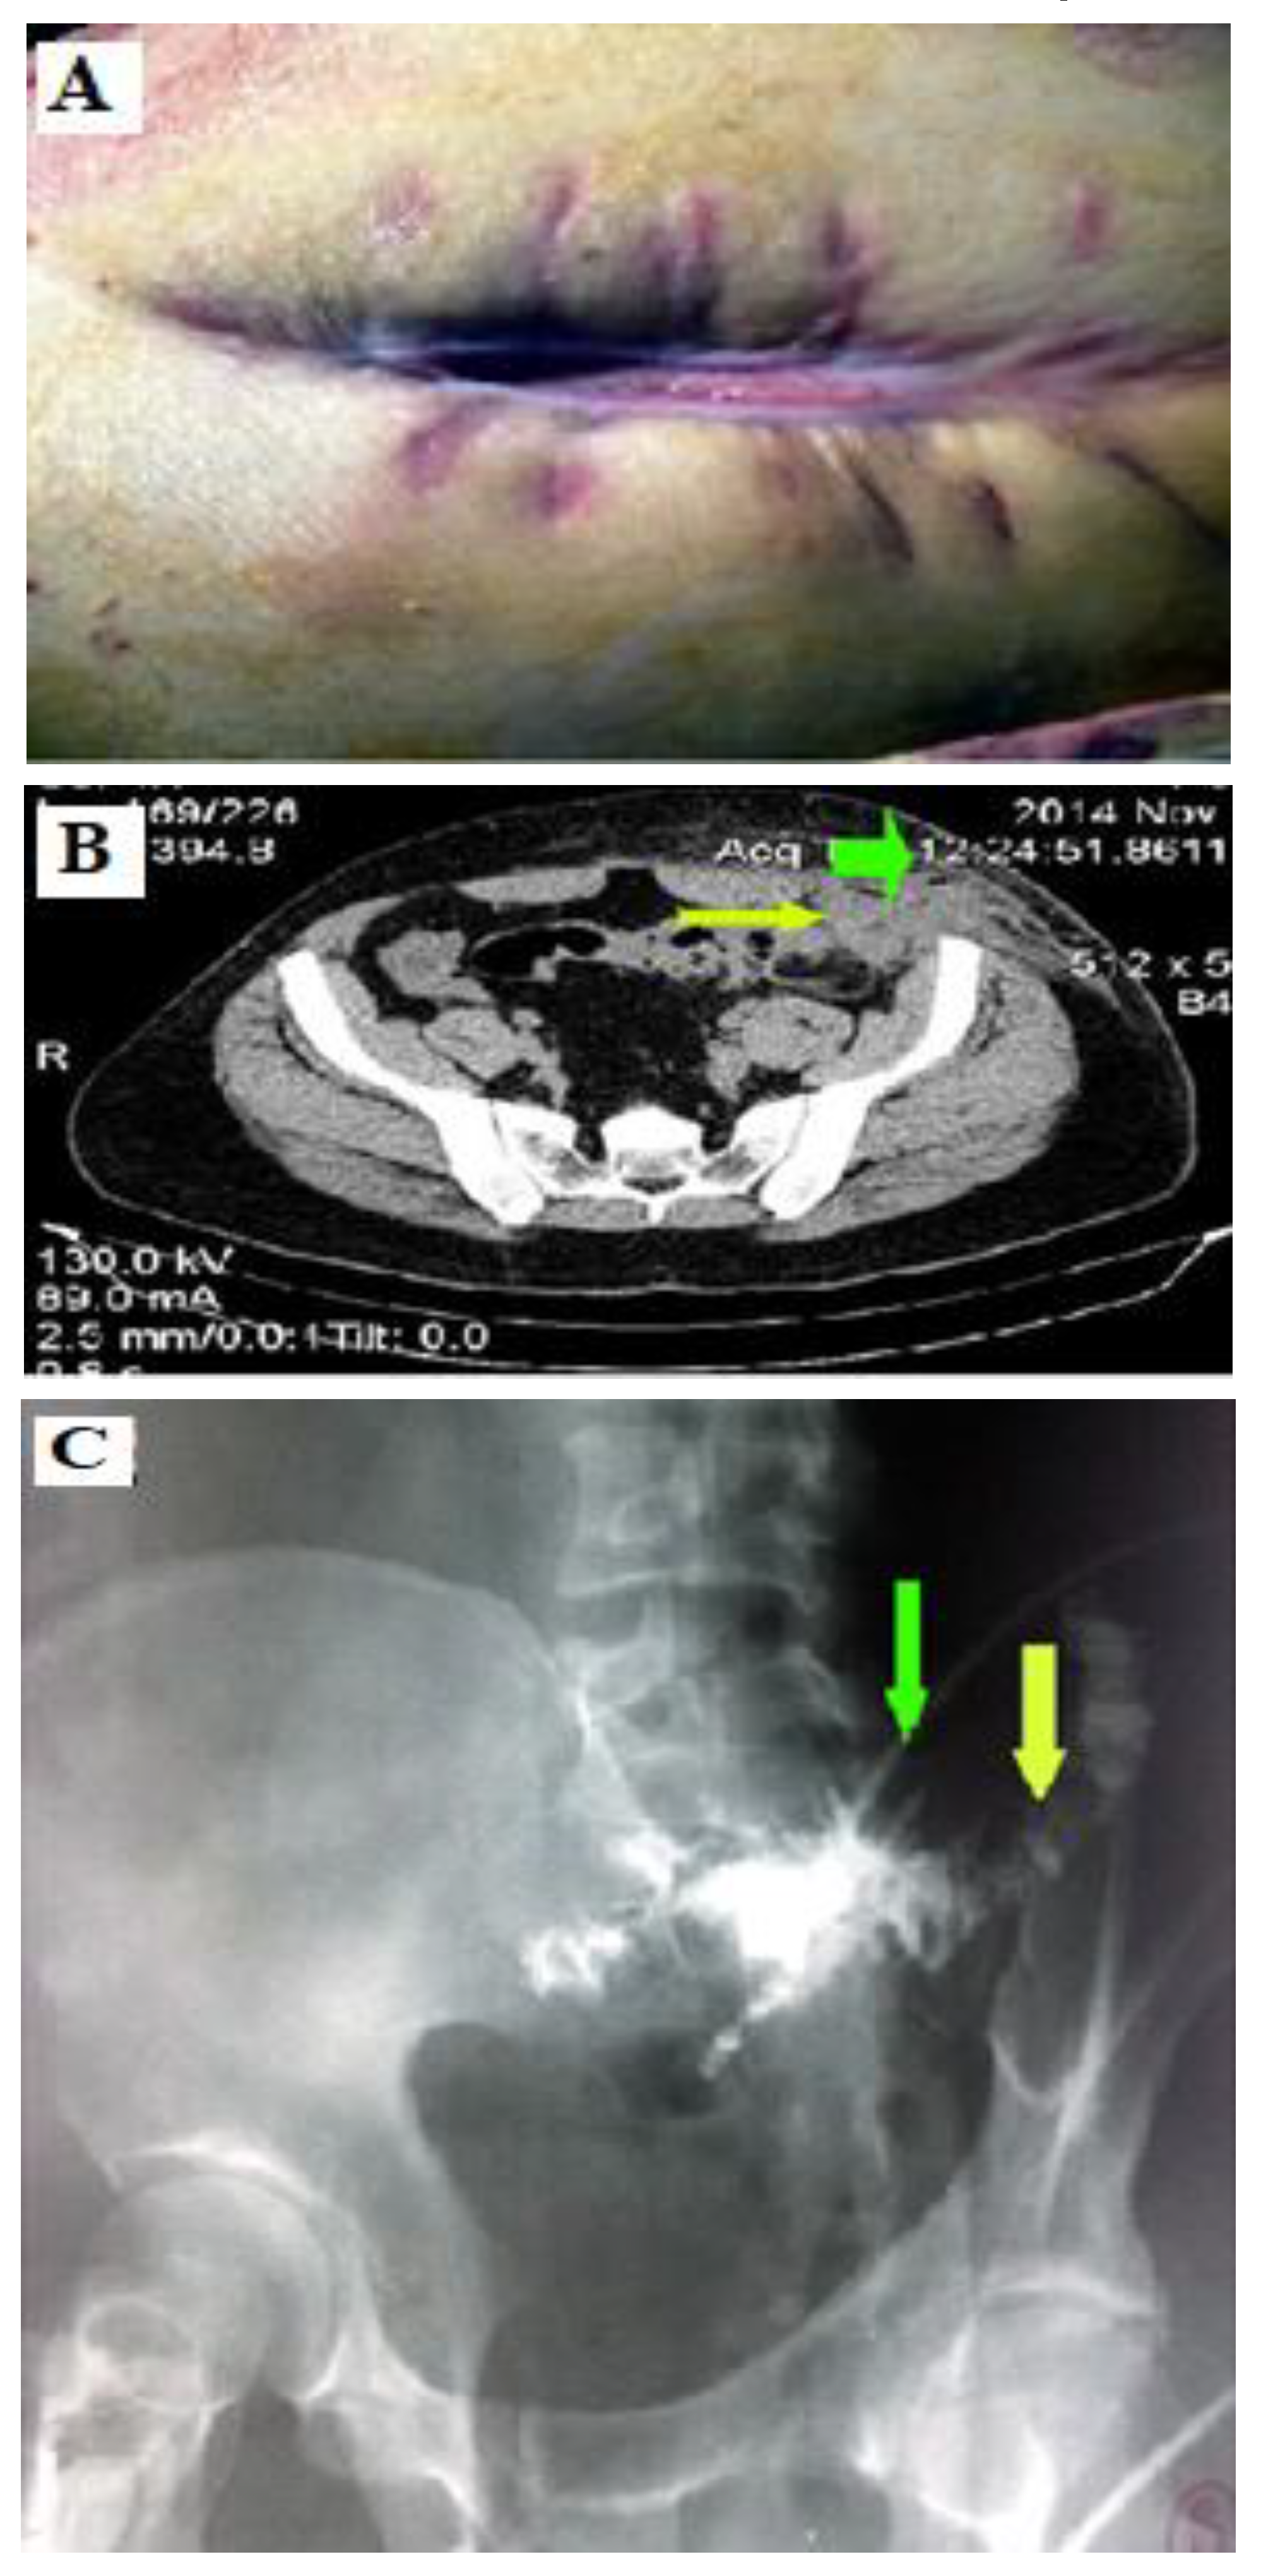

A 45-year-old male patient was hospitalized to the Second Surgical Clinic of the Emergency County Hospital in Craiova in January 2015 for cutaneous fistula and sero-purulent secretion through a fistulous orifice located in the left iliac fossa. The patient underwent surgery three months before for parietal abscess in the left iliac fossa when the collection was evacuated. The postoperative evolution was unfavorable with the formation of a fistulous orifice at the level of the postoperative scar in the left iliac fossa (Figure 2A).

The physical examination indicated the presence of a postoperative scar with signs of inflammation and, at its lower pole, a fistulous orifice with a diameter of 0.2-0.3 cm through which sero-purulent fluid is evacuated. The fistulography of the left iliac fossa was performed using a small tube that was inserted into the fistulous orifice and showed the opacification of the sigmoid loop up to 2 cm in diameter with oblique-transverse trajectory, with ascending direction to the left flank; the sigmoid colonic mucosa also had inflammatory changes and incomplete luminal stenosis over a distance of about 10 cm (Figure 2C).

The abdominal and pelvic CT showed the infiltration of the subcutaneous fat with inflammatory aspect in the anterior and left abdominal wall, extended to the pelvic rectum, external oblique, internal oblique and transverse. For the lower pole of the postoperative scar, the inflammatory process spread to the intrapelvic region without extending to the left iliac muscle, and without a cleavage plane to the ileal loops. It also showed the presence of a fluid collection and areas of air bubbles in the muscles of the abdominal wall (Figure 2B). During surgery, an inflammatory process was found in the left iliac fossa involving the sigmoid colon, the anterior abdominal wall, and the large omentum (Figure 3A). The release of the sigmoid loop was difficult and the presence of a fistulous orifice with a diameter of 0.4-0.5 cm was found, with a thickened wall and irregular edges. Sigmoidectomy was performed with end-to-end colorectal anastomosis. The postoperative piece consisted of a sigmoid colon segment with a length of 25 cm (Figure 3C), which turned out to contain a perforated diverticulum (when sectioned) located antimezosthenically (Figure 3B). The postoperative evolution was favorable. The patient was discharged after 7 days without complications.

Jmms 09 00015 g001

Figure 2. A. The objective clinical examination showed the presence of a fistulous orifice at the lower pole of the postoperative scar, through which a sero-purulent secretion is externalized; B. The abdominal and pelvic CT of the patient with colo-cutaneous fistula: the presence of a fluid collection and areas of air bubbles in the muscles of the abdominal wall (green arrow) and the disappearance of the cleavage plane with the small intestine (yellow arrow); C. Fistulography: a tube is visualized in the left iliac fossa (green arrow)—the small intestine is opacified, with a diameter of up to 2 cm, with an oblique-transversal trajectory (yellow arrow).